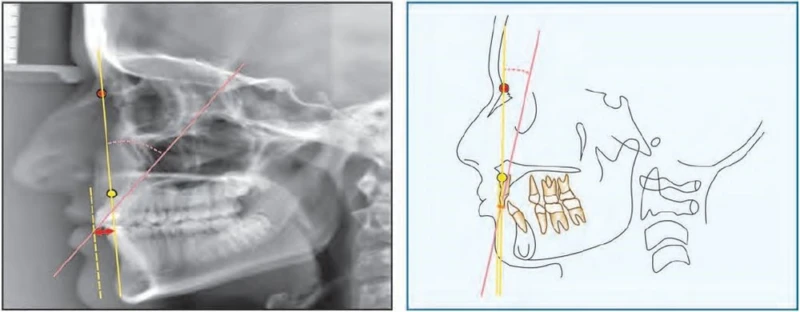

Góc mặt phẳng nhai

Mặt phẳng nhai được vẽ từ vùng lồng múi của các răng cối nhỏ và răng cối lớn thứ nhất. Đo giá trị góc tạo tạo bởi mặt phẳng nhai với mặt phẳng SN.

Giá trị trung bình của góc này ở người có khớp cắn bình thường là 14 độ. Góc này tăng trong trường hợp mặt dài hoặc tăng trưởng theo chiều dọc và cũng gặp trong những trường hợp cắn hở xương. Góc này có thể giảm trong trường hợp tăng trường theo chiều ngang hoặ cắn sâu xương.

Góc mặt phẳng hàm dưới

Mặt phẳng hàm dưới được vẽ từ Go đến Gn. Góc mặt phẳng hàm dưới được tạo thành bằng cách nối mặt phẳng hàm dưới với nền sọ trước (mặt phẳng S-N).

Giá trị trung bình của góc này là 32 độ.

Góc mặt phẳng hàm dưới lớn (tăng trưởng theo chiều dọc) hoặc nhỏ (tăng trưởng theo chiều ngang) cho thấy những dạng tăng trưởng không thuận lợi và có thể gây ảnh hưởng đến kết quả điều trị.